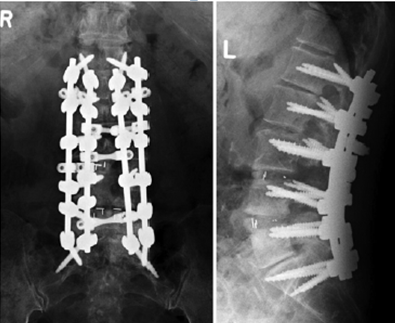

(5)内固定方式选择

内固定融合区固定强度过大,如全椎弓根螺钉固定和多棒固定。

融合区内固定强度越坚固,PJK的发生风险越高。

图12 CBT+TT+多棒固定

CBT+TT+多棒固定